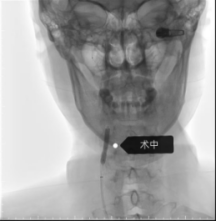

手术当日,神经内科介入团队娴熟操作介入设备,导丝、导管、支架系统操作顺利送达指定部位,成功将支架输送至狭窄部位并精准释放,瞬间打通了狭窄严重的血管,恢复了大脑的正常供血,整台手术流畅顺利,采用局部麻醉,患者全程清醒,无身体不适反应。